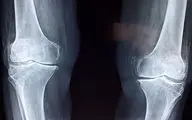

فوق تخصص بیماریهای روماتولوژی با اشاره به اهمیت پیشگیری و تشخیص زودهنگام پوکی استخوان گفت: این بیماری به کاهش مواد…